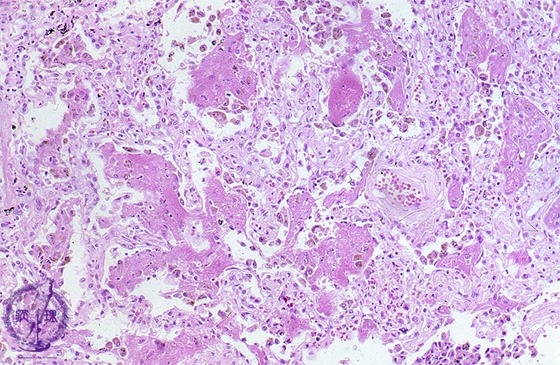

Microscopic view (HE stain, low power view): Prominent alveolar fibrin deposition with septal edema, congestion and a cellular infiltrate are seen. Note that, unlike in bronchopneumonia, alveolar structure is preserved.